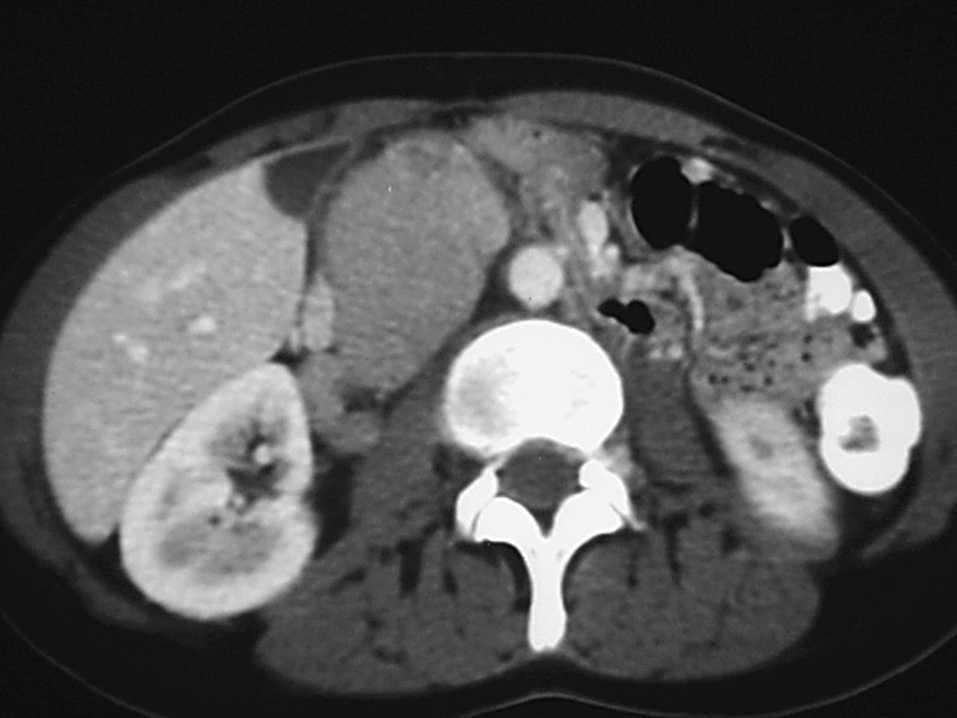

La paciente era una joven de 28 años que venía siendo largamente estudiada por el Servicio de Medicina Interna por un cuadro de anemia crónica. Sus antecedentes eran una alergia a penicilina, tabaquismo y los últimos 2 años en tratamiento para la infertilidad. La exploración era normal, salvo la palpación del abdomen, en la que se delimitaba una tumoración adherida a planos profundos en hipocondrio derecho, no dolorosa. No había adenomegalias. Todos los numerosos y exhaustivos estudios realizados fueron negativos. Sólo se pudo evidenciar una infección por citomegalovirus con posterior negativización de IgM. En la tomografía computarizada (fig. 1) se definían imágenes nodulares múltiples entre la aorta y la cava y retrocavas por debajo de la salida de la mesentérica superior, de 2,5 y 2,2 cm. En continuidad y en sentido distal, se observa un gran nódulo de 6,7 x 4,7 cm que llega a la pared abdominal. El resto de la exploración descartaba la existencia de otras adenopatías.

Fig. 1. TAC. Tumoración retroperitoneal interaórtico-cava.